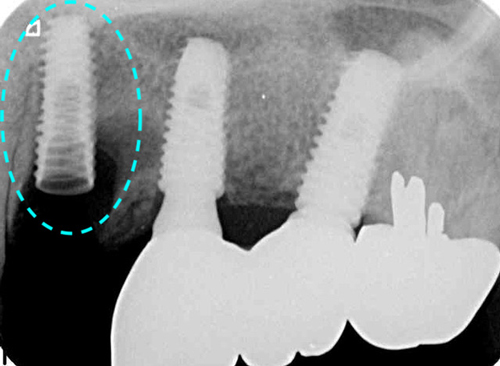

レントゲンCT画像分析の結果、動いているのはインプラントの1本手前のご自身の歯牙であることが判明しました。

上記は、おそらく根が割れているのでは?と思われるレントゲン画像です。